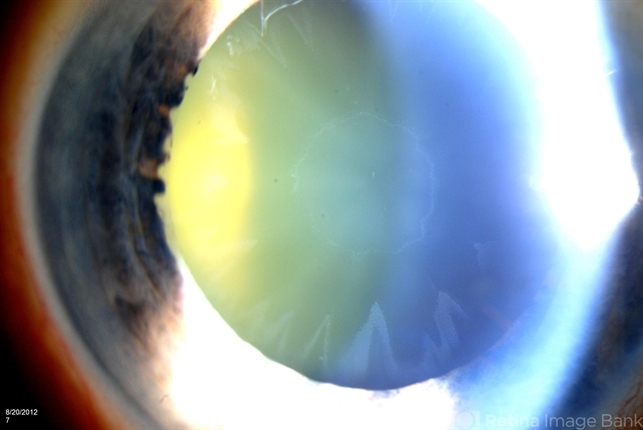

- pseudoexfoliation glaucoma

- Jason S. Calhoun, Mayo Clinic Jacksonville, Florida

- Photo slit lamp biomicroscope

- Patient's VA 20/50 with pinhole no improvement. Patient will have cataract surgery in the future. Notice pseudoexfoliation ring centrally.